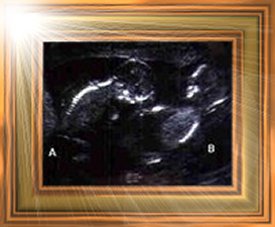

Zaryn Ryann-Amara

(Twin A)

November 18, 2002 @ 16 weeks gestation